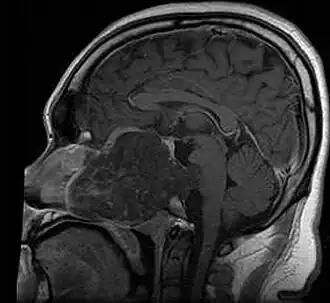

| MRI of extensive clival chordoma in 17-year-old male patient, axial view. Tumor in the nasopharynx extending from nasal cavity to brainstem posteriorly is clearly visible. | |

Chordoma is a rare slow-growing neoplasm (cancer) that arises from cellular remnants of the notochord in the bones of the skull base and spine. The evidence for the notochordal origin of chordoma is the location of the tumors (along the neuraxis), the similar immunohistochemical staining patterns, expression of brachyury, and the demonstration that notochordal cells are preferentially left behind in the clivus and sacrococcygeal regions when the remainder of the notochord regresses during fetal life.

In layman's terms, chordoma is a type of bone cancer, and is classified as a sarcoma.[1] Chordomas are sometimes mistakenly referred to as a brain, brainstem or spinal cord tumors due to their location near those critical structures, but they are not derived from nervous tissue.

Chordomas can arise from bone in the skull base and anywhere along the spine. The two most common locations are cranially at the clivus and in the sacrum at the bottom of the spine.[2] Very rarely, chordomas present outside of the skull base or spine; these are called extra axial chordomas.[3]